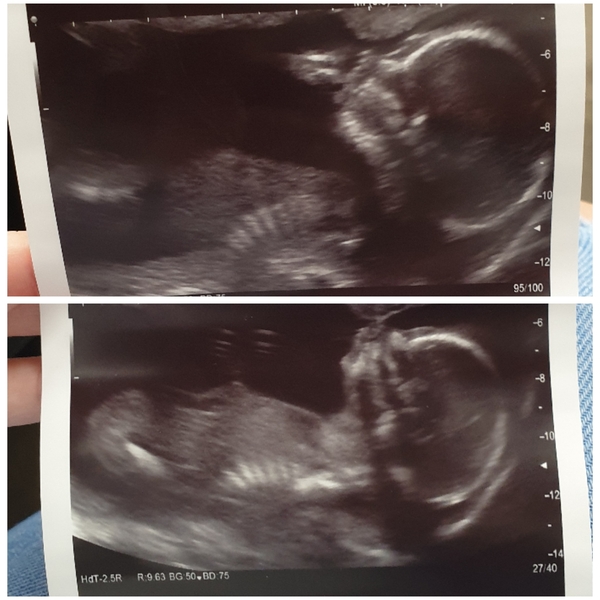

Had my scan today very happy healthy 💕GIRL 💕

@Zoey92 congratulations lovely pictures!

I love seeing ultrasounds! 🥰